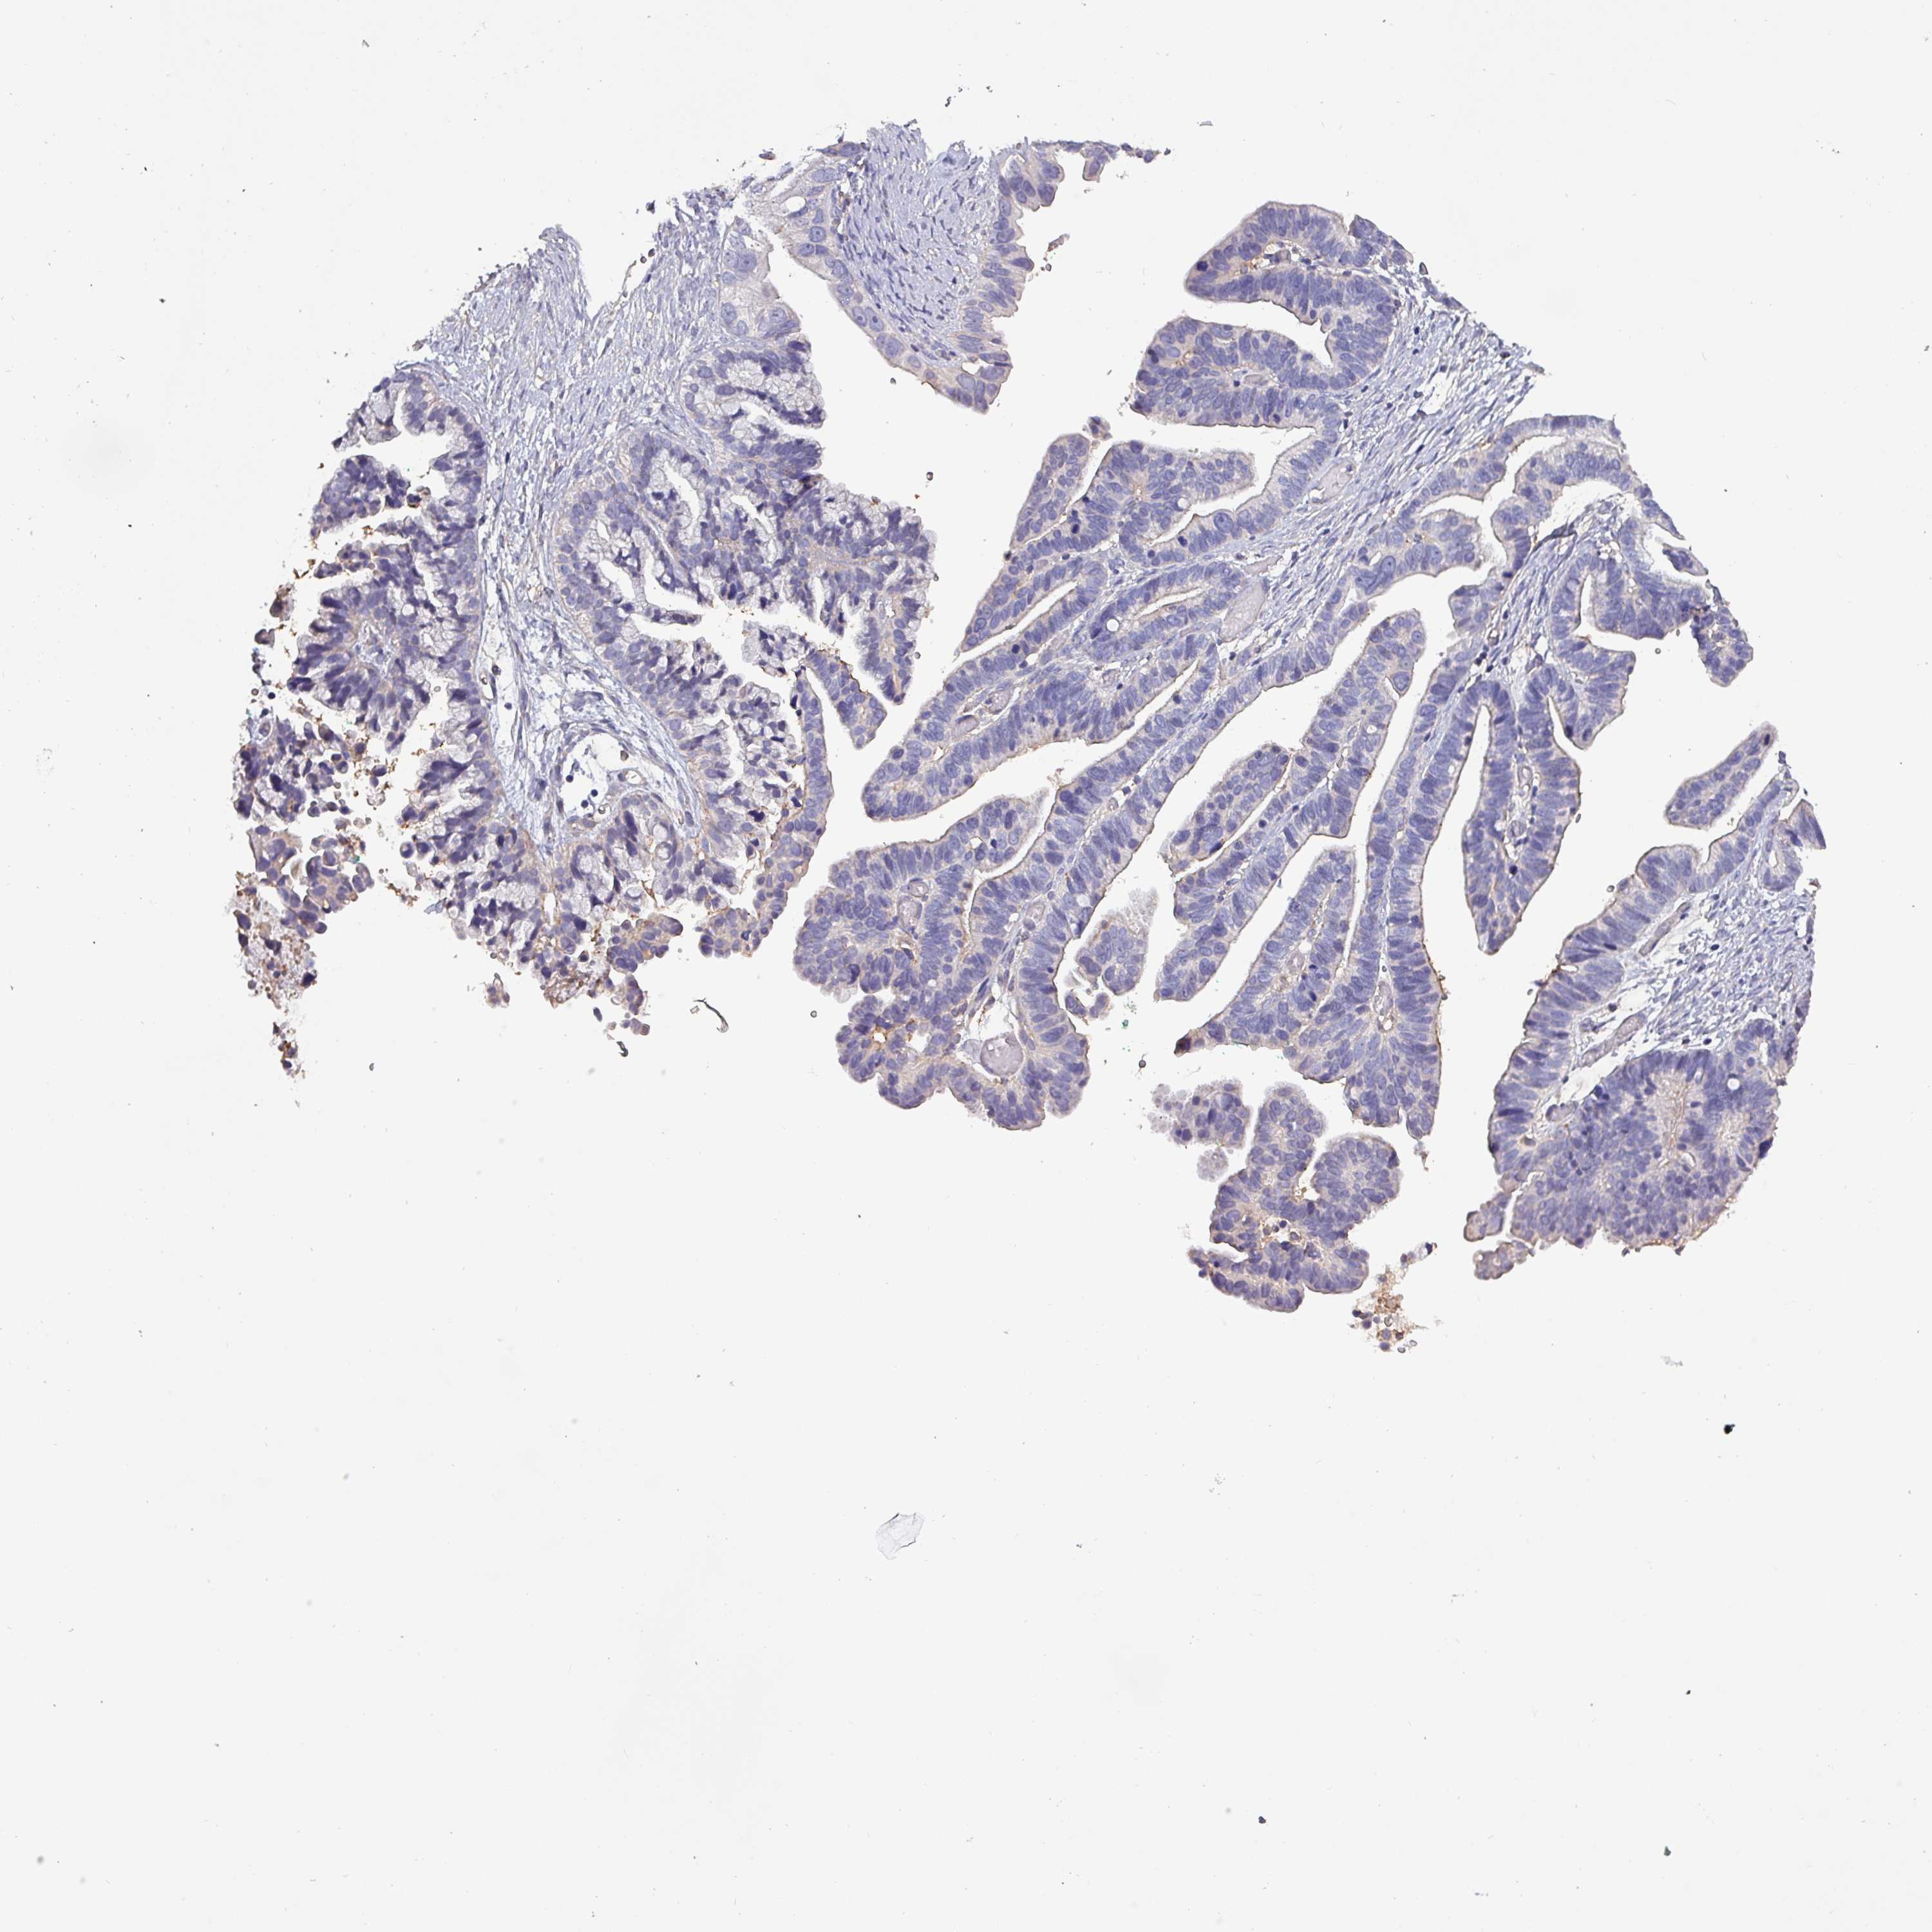

OVARIAN CANCER - Protein expressioni

A mouse-over function shows sample information and annotation data. Click on an image to view it in a full screen mode. Samples can be filtered based on level of antibody staining by selecting one or several of the following categories: high, medium, low and not detected. The assay and annotation is described here.

Note that samples used for immunohistochemistry by the Human Protein Atlas do not correspond to samples in the TCGA dataset.

Antibody stainingi

Antibody staining in the annotated cell types in the current human tissue is reported as not detected, low, medium, or high, based on conventional immunohistochemistry profiling in selected tissues. This score is based on the combination of the staining intensity and fraction of stained cells.

Each image is clickable and will lead to virtual microscopy that enables deeper exploration of all samples and also displays staining intensity scores, fraction scores and subcellular localization as well as patient and tissue information for each sample.

Antibody HPA045402

Staining

High

Medium

Low

Not detected

Intensity

Strong

Moderate

Weak

Negative

Quantity

>75%

75%-25%

<25%

None

Location

Nuclear

Cytoplasmic/membranous

Cytoplasmic/membranous,nuclear

Cystadenocarcinoma, serous, NOS

Carcinoma, endometroid

Cystadenocarcinoma, mucinous, NOS

Carcinoma, NOS